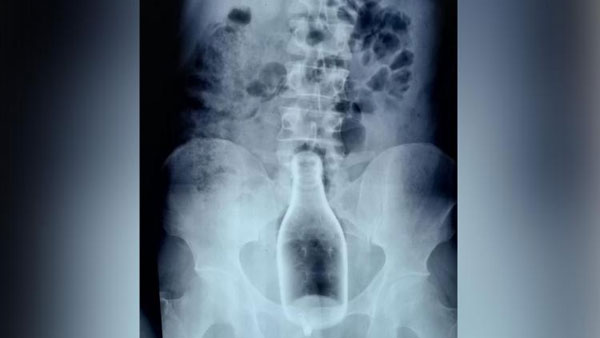

షాకింగ్: మలద్వారంలో మందు బాటిల్.. నెవర్ బిఫోర్ అంటున్న డాక్టర్లు.. తమిళనాడులో సీన్ ఇది..

ఇప్పటిదాకా మందుబాబులకు సంబంధించిన విచిత్ర కథనాలెన్నో చదివాం. ఇది మాత్రం నెవర్ బిఫోర్ అని డాక్టర్లే అంటున్నారు. ''నా సుదీర్ఘ కెరీర్ లో ఇలాంటి వింత కేసును ఎప్పుడూ చూచలేదు''అని వాపోయారు నాగపట్నం ప్రభుత్వాసుపత్రి జనరల్ సర్జన్ డాక్టర్ పాండియరాజ్. రెండ్రోజుల కిందట ఆయన డీల్ చేసిన కేసు తాలూకు ఫొటోలు, వార్తలు వైరల్ అయ్యాయి. ఓ వ్యక్తి మలద్వారంలో చిక్కుకుపోయిన మద్యం బాటిట్ ను సర్జరీ ద్వారా తొలగించారాయన. గోప్యత దృష్ట్యా బాధితుడి పేరు వెల్లడించకుండా అసలేం జరిగిందో డాక్టర్ పాండియరాజ్ చెప్పారిలా..

నాగపట్నం జిల్లాలోని నాగూరు చెందిన 29 ఏళ్ల యువకుడు.. రెండ్రోజుల కిందట జిల్లా ఆస్పత్రికి వచ్చాడు. మలద్వారంలో భరించలేని నొప్పి ఉన్నట్లు చెప్పడంతో ముందుగా ఎక్స్ రే తీయించారు. ఆ రిపోర్టుల్లో.. ‘మ్యాన్షన్ హౌస్' బ్రాండ్ను పోలిన క్వార్టర్ బాటిల్ అతని లోపల చిక్కుకుపోయినట్లు వైద్యులు గుర్తించారు. అయితే, అతనికి ఆపరేషన్ చేయాలంటే.. ముందుగా కరోనా టెస్టులు చేయాలనే నిబంధన ఉంది. కరోనా రిజల్ట్ వచ్చేలోపు.. లోపలున్న గాజు సీసా పగిలిపోతే అతని ప్రాణాలకు ప్రమాదం ఏర్పడొచ్చని భావించిన డాక్టర్లు.. హుటాహుటిన సర్జరీ చేశారు..

సుమారు రెండున్నర గంటలపాటు శ్రమించిన డాక్టర్లు.. చివరికి ఆ వ్యక్తి మలద్వారంలో చిక్కుకున్న మద్యం బాటిల్ ను బయటికి తీశారు. సున్నితమైన భాగాలు కొద్దిగా దెబ్బతినడంతో మరో నాలుగైదురోజులు ఆస్పత్రిలోనే ఉండాల్సిందిగా సూచించారు. అసలీ ఘటనకు కారణం మద్యమేనని డాక్టర్ పాండియరాజ్ చెప్పారు. ‘‘మద్యం మత్తులో ఏం చేస్తున్నాడో తెలియని స్థితిలో తాను తాగిన బాటిల్ ను మలద్వారంలోకి గుచ్చుకున్నాడు. సగం దూరిన తర్వాత వెనక్కి లాగడానికి ప్రయత్నించగా అది రాలేదు. దీంతో మొత్తం బాటిల్ ను బలవంతంగా లోపలికి నెట్టుకున్నాడు. మత్తు దిగిన తర్వాత నొప్పి ఉన్నప్పటికీ, ఈ సంగతి ఎవరికనా చెబితే పరువు పోతుందని భావించి, రెండు రోజులు అలాగే ఉండిపోయాడు. చివరికి నొప్పి తాళలేని స్థితిలో ఆస్పత్రికి వచ్చాడు''అని వివరించారు.